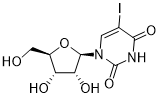

馬鞍山致研生物醫(yī)藥科技有限公司成立于馬鞍山市鄭浦港新區(qū)現(xiàn)代產(chǎn)業(yè)園。公司專(zhuān)注于生物小分子、醫(yī)藥中間體相關(guān)產(chǎn)品的研發(fā)和生產(chǎn),產(chǎn)品主要包括DNA亞磷酰胺單體、RNA亞磷酰胺單體、特殊單體以及按照客戶(hù)要求定制的RNA和DNA,并且公司提供定制合成等方面的研究服...

馬鞍山致研生物醫(yī)藥科技有限公司成立于馬鞍山市鄭浦港新區(qū)現(xiàn)代產(chǎn)業(yè)園。公司專(zhuān)注于生物小分子、醫(yī)藥中間體相關(guān)產(chǎn)品的研發(fā)和生產(chǎn),產(chǎn)品主要包括DNA亞磷酰胺單體、RNA亞磷酰胺單體、特殊單體以及按照客戶(hù)要求定制的RNA和DNA,并且公司提供定制合成等方面的研究服...